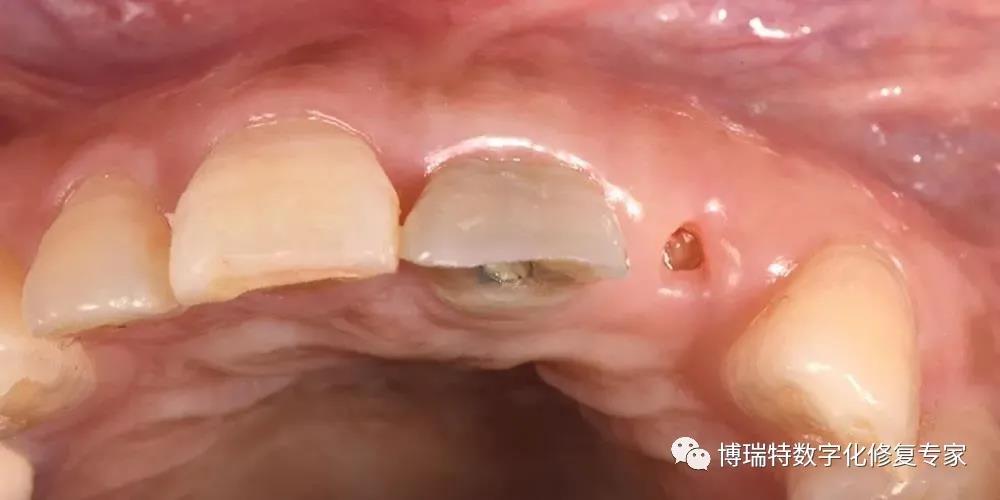

8226; 术后一周,21牙龈冠向生长;

8226; 术后一月,21残根磨至龈下。

牙龈诱导

8226; 四个月后,取下临时修复体,见21牙龈高度与11基本一致,穿龈轮廓初步成形,22牙龈基本覆盖断根面;